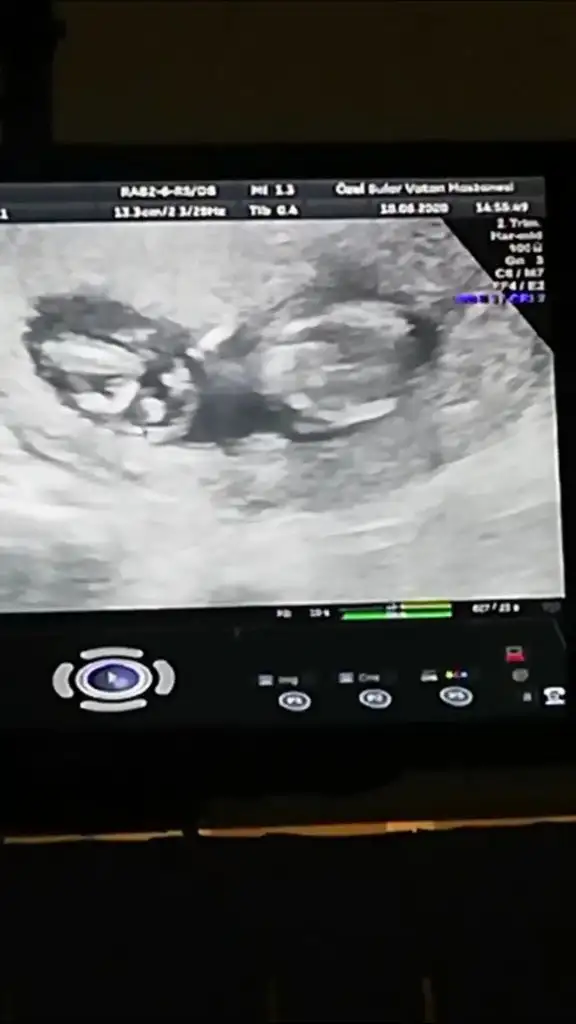

Merhabaaa ben de cinsiyetten emin olamayan doktor mağduruyum yardımcı olur musunuz

İlk fotoğraf 12+0

İkinci fotoğraf 12+3 (doktor çıkıntı gördüm sanki ama kesin değil dedi)

Üçüncü fotoğraf 14+2 (kız gibi dedi ama bakmaya devam ederken aaa pipi bu ama yine de emin olmak için 1-2 hafta sonra tekrar bakalım dedi)

son fotoğraf da gördüm dediği pipi